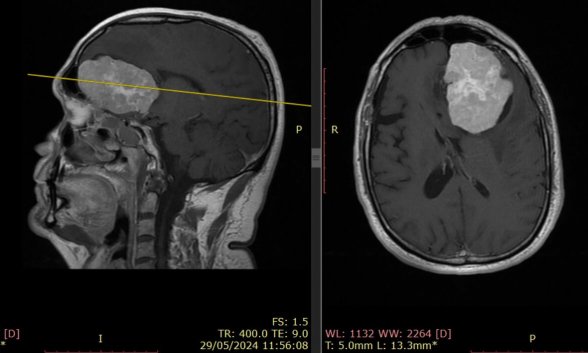

Ante este panorama, la ciencia ha intensificado sus esfuerzos para mejorar el diagnóstico y tratamiento de estos tumores. Uno de los grandes avances ha sido la incorporación de técnicas de imagen y cirugía de alta precisión. Gracias a la neuroimagen avanzada, la navegación quirúrgica y la cirugía guiada por fluorescencia, hoy es posible localizar el tumor con gran exactitud y extirparlo minimizando daños en el tejido sano. Esto ha reducido riesgos y mejorado la calidad de vida de los pacientes operados.

Gracias a la neuroimagen avanzada, la navegación quirúrgica y la cirugía guiada por fluorescencia, hoy es posible localizar el tumor con gran exactitud y extirparlo minimizando daños en el tejido sano. Esto ha reducido riesgos y mejorado la calidad de vida de los pacientes operados